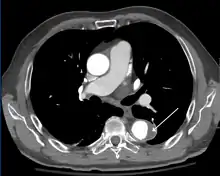

Computed tomography angiography is a fast, non-invasive test that gives an accurate three-dimensional view of the aorta. These images are produced by taking rapid, thin-cut slices of the chest and abdomen, and combining them in the computer to create cross-sectional slices. To delineate the aorta to the accuracy necessary to make the proper diagnosis, an iodinated contrast material is injected into a peripheral vein. Contrast is injected and the scan performed using a bolus tracking method. This type of scan is timed to injection to capture the contrast as it enters the aorta. The scan then follows the contrast as it flows through the vessel. It has a sensitivity of 96 to 100% and a specificity of 96 to 100%. Disadvantages include the need for iodinated contrast material and the inability to diagnose the site of the intimal tear.

CT with contrast demonstrating aneurysmal dilation and a dissection of the ascending aorta (type A Stanford)

Chest CT with descending (type B Stanford) aortic dissection (red circle)